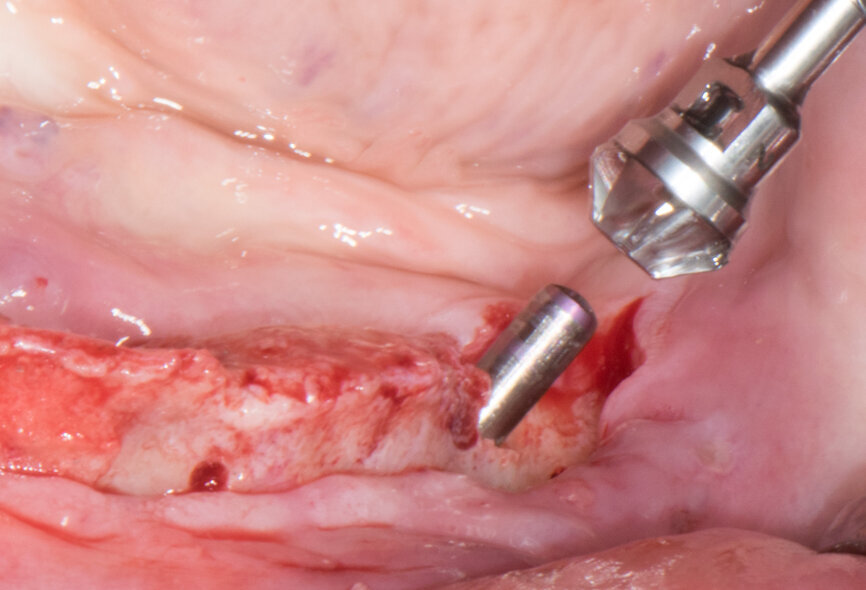

Implant beds were prepared (Figs. 13 & 14) and Straumann BLT implants placed with a torque setting of more than 35 Ncm, following the protocol to allow correct subsequent screw retained abutment placement (Figs. 15 & 16). Bone around the implants was prepared with bone profilers (Straumann) for the same reason (Fig. 17). The crest was flattened (Figs. 18 & 19), screw-retained abutments were screwed to 35 Ncm (Fig. 20) and covered with healing caps, and the wound was sutured (Fig. 21).